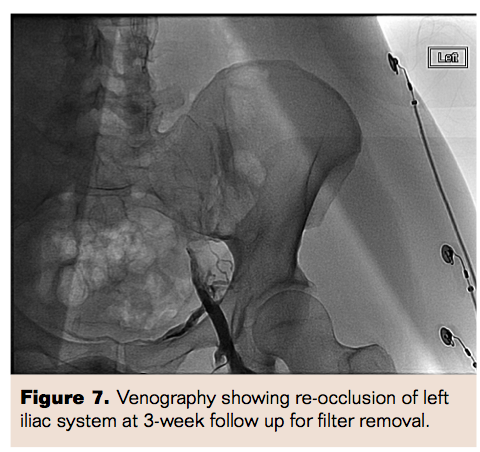

Three weeks later, she was brought back to the cardiac catheterization laboratory for venography and for possible removal of the IVC filters. Venography revealed re-occlusion of the left iliac system secondary to thrombus. A decision was made to proceed with balloon angioplasty of the left iliac system. After multiple balloon dilatations, intravascular ultrasound (IVUS) was performed, which revealed compression of the left iliac vein by the right iliac artery. Two self-expanding 12 mm x 60 mm and 10 mm x 60 mm Protégé GPS self-expanding stents (Covidien Inc) were then deployed into the left common iliac venous system. There was excellent flow through the stents via both wide-open bilateral IVC and pelvic connectors. We chose not to remove the IVC filters at this juncture because of the presence of extensive clot burden. The pelvic connector between left IVC and right iliac vein was noted to be behind the aortoiliac bifurcation and was compressed. IVUS of the pelvic connector was performed, which confirmed the suspicion of compression. After performing balloon dilatation of the compression, a 12 mm x 40 mm Protégé GPS self-expanding stent was deployed which subsequently showed excellent flow in the connector and in bilateral IVC.